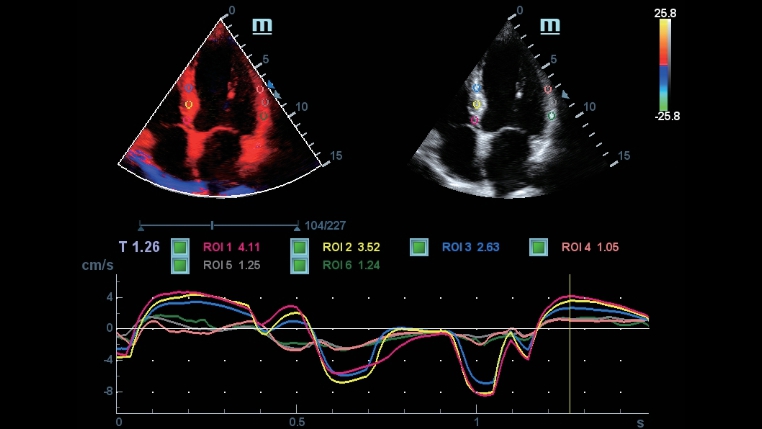

Berbagai macam alat bantu aplikasi: menjamin akurasi dengan kenyamanan iTouch

DC-40 dengan Full HD menghadirkan berbagai macam alat bantu yang memaksimalkan akurasi diagnostik dengan kenyamanan. Mencakup Pencitraan Umum, OB/GYN dan Kardiologi, DC-40 dengan Full HD bisa menghadirkan solusi lengkap bagi aplikasi klinis umum/mainstream, dengan alur kerja yang disederhanakan demi memastikan efisiensi.

Smart Track

Smart Track menyediakan optimasi yang cepat dan cerdas untuk pencitraan vaskular dengan operasi satu sentuhan yang sederhana. Alat ini bisa mengoptimalkan spektrum Warna, Daya, dan PW dengan melakukan pelacakan mandiri dan mengurangi langkah-langkah yang menghabiskan waktu. Oleh karena itu, alur kerja pemeriksaan vaskular disederhanakan dengan tampilan yang optimal.